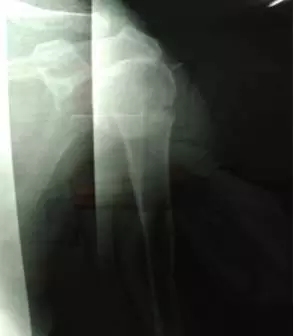

70多岁的鲍阿婆在家人陪同下来到上海大团医院就诊。大团医院的医生给鲍阿婆左肩部做了X线片检查。片子拍出来竟然是左肱骨近端粉碎性骨折。外科颈,大结节都碎了,而且骨折端移位很严重。

正骨科的虞杰主任、邵鹏及叶华磊医生看到鲍阿婆的片子也是一皱眉头,这么厉害的骨折,还真是少见,而且移位这么严重,手法复位的难度也是相当大的。不过患者的信任给了他们很大的动力,即使困难也要尽力帮患者。

整复后复查X线片,骨折端位置良好。

整复前